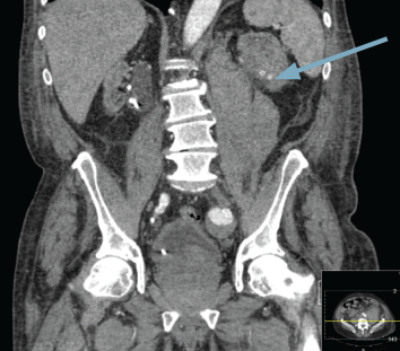

A 76-year-old male with end stage renal failure due to obstructive uropathy from benign prostatic enlargement was transferred from a referring hospital. A right ureteric stent had been placed and a left sided stent was sited too far proximally in the ureter (Figure 1). Comorbidity included ischaemic heart disease, cardiac failure and the patient was anti-coagulated. There had been one failed attempt to re-position the stent.

Figure 1.

Blush of contrast in left kidney during arterial phase CT.